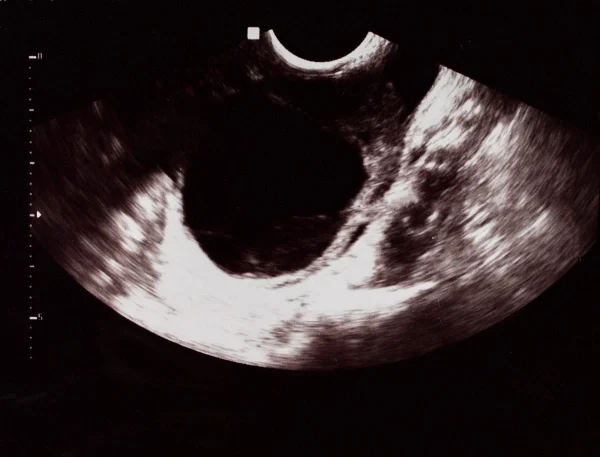

O diagnóstico do cisto hemorrágico é realizado por um ginecologista a partir de uma avaliação clínica detalhada, considerando os sintomas relatados pela paciente. Exames de imagem, como o ultrassom transvaginal, são fundamentais para visualizar o cisto e identificar características sugestivas de conteúdo hemorrágico.